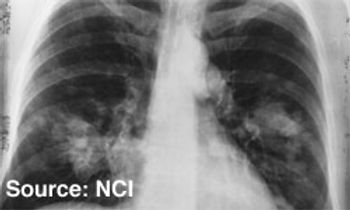

New treatments that are currently in development have begun to show promise for patients diagnosed with ALK-positive non-small-cell lung cancer (ALK+ NSCLC), a subset of patients who have historically faced poor outcomes.